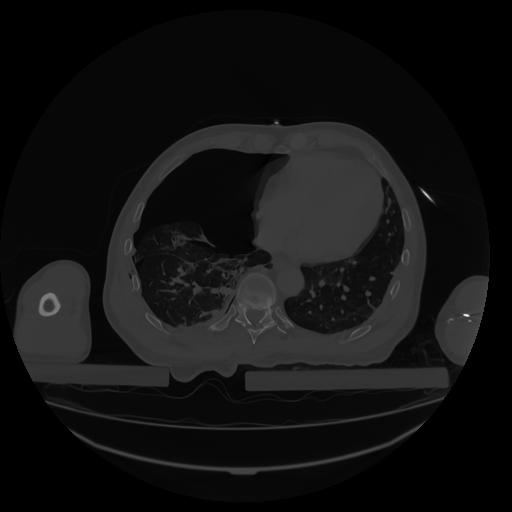

34 CUERPO,CE,Vol,1.0,CUERPO,,